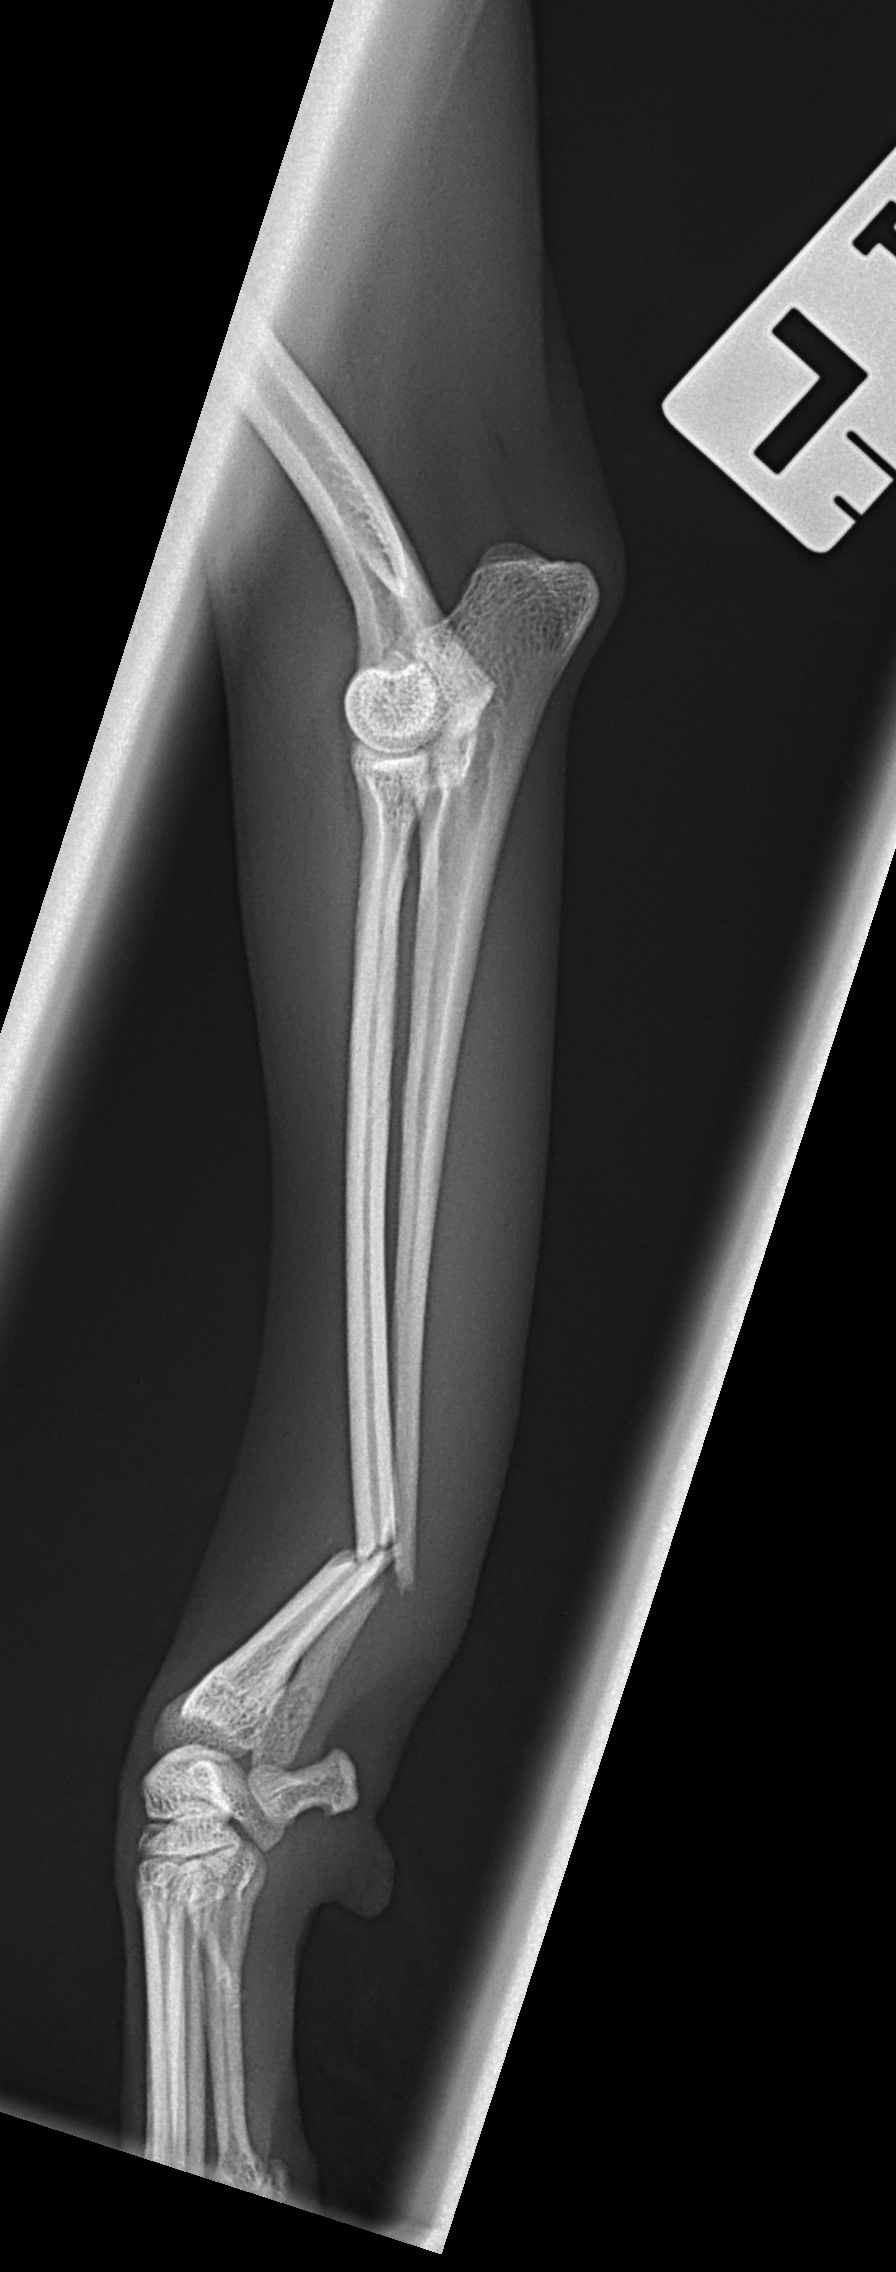

橈骨固定術 #249 Toy Poodleさんがソファーからジャンプして橈骨骨折をしたとのことで主治医の先生から固定術の依頼がありました。1.5 Titanium Locking Plateで固定術を行いました。しばらくは安静が必要です。 症例カテゴリー 放射線治療整形外科軟部組織外科脳神経外科内科腫瘍外科救急・集中治療リハビリテーション科腫瘍内科内視鏡科脳神経科呼吸器外科中医・漢方猫の腎移植循環器科